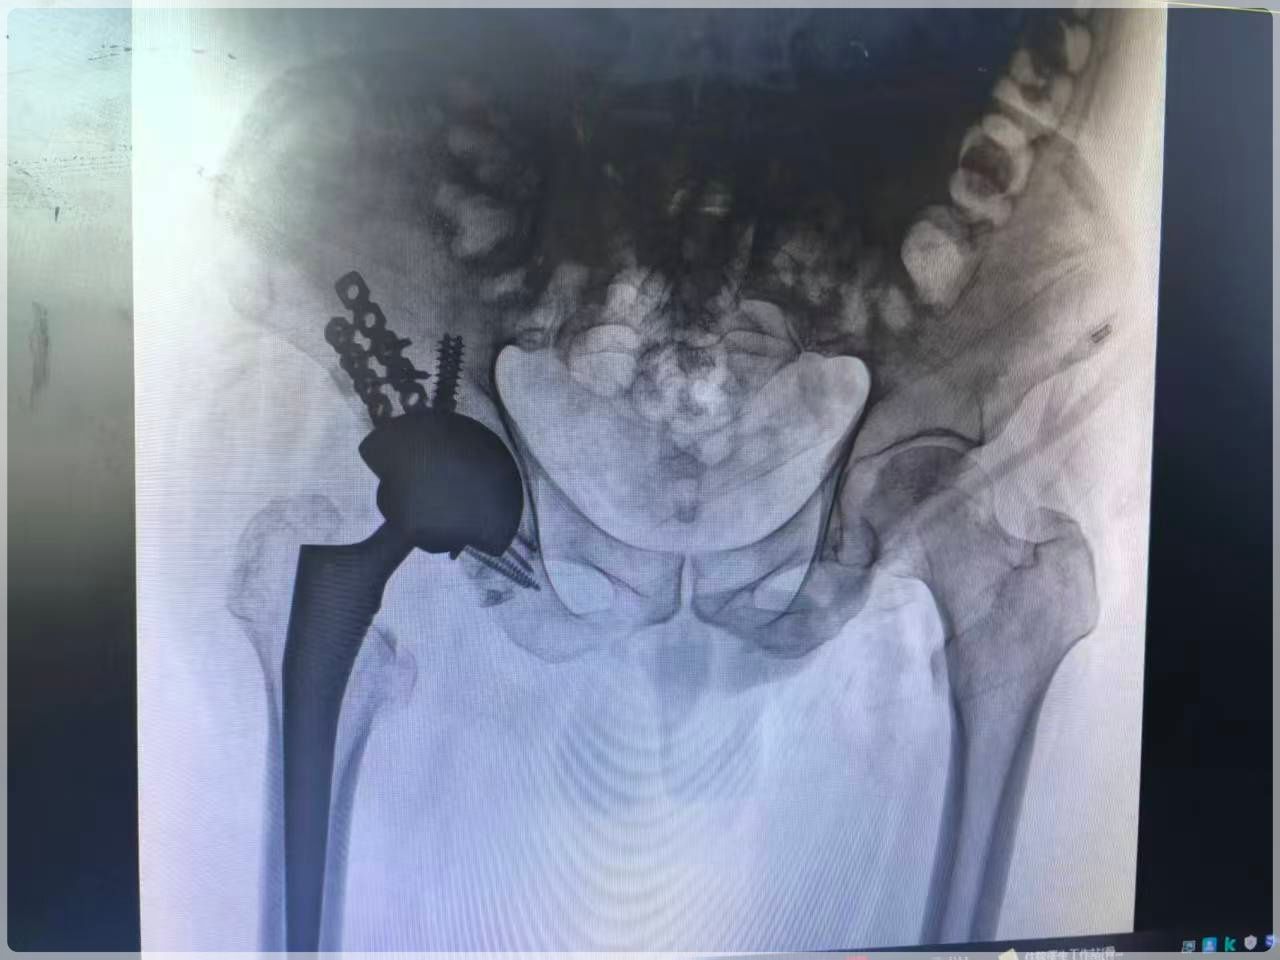

术后影像显示,假体位置、角度完全符合术前规划,双下肢长度恢复对称。赵先生疼痛迅速缓解,在康复科团队指导下早期下床活动,功能恢复明显快于常规手术,目前已顺利康复出院。

(术后影像)